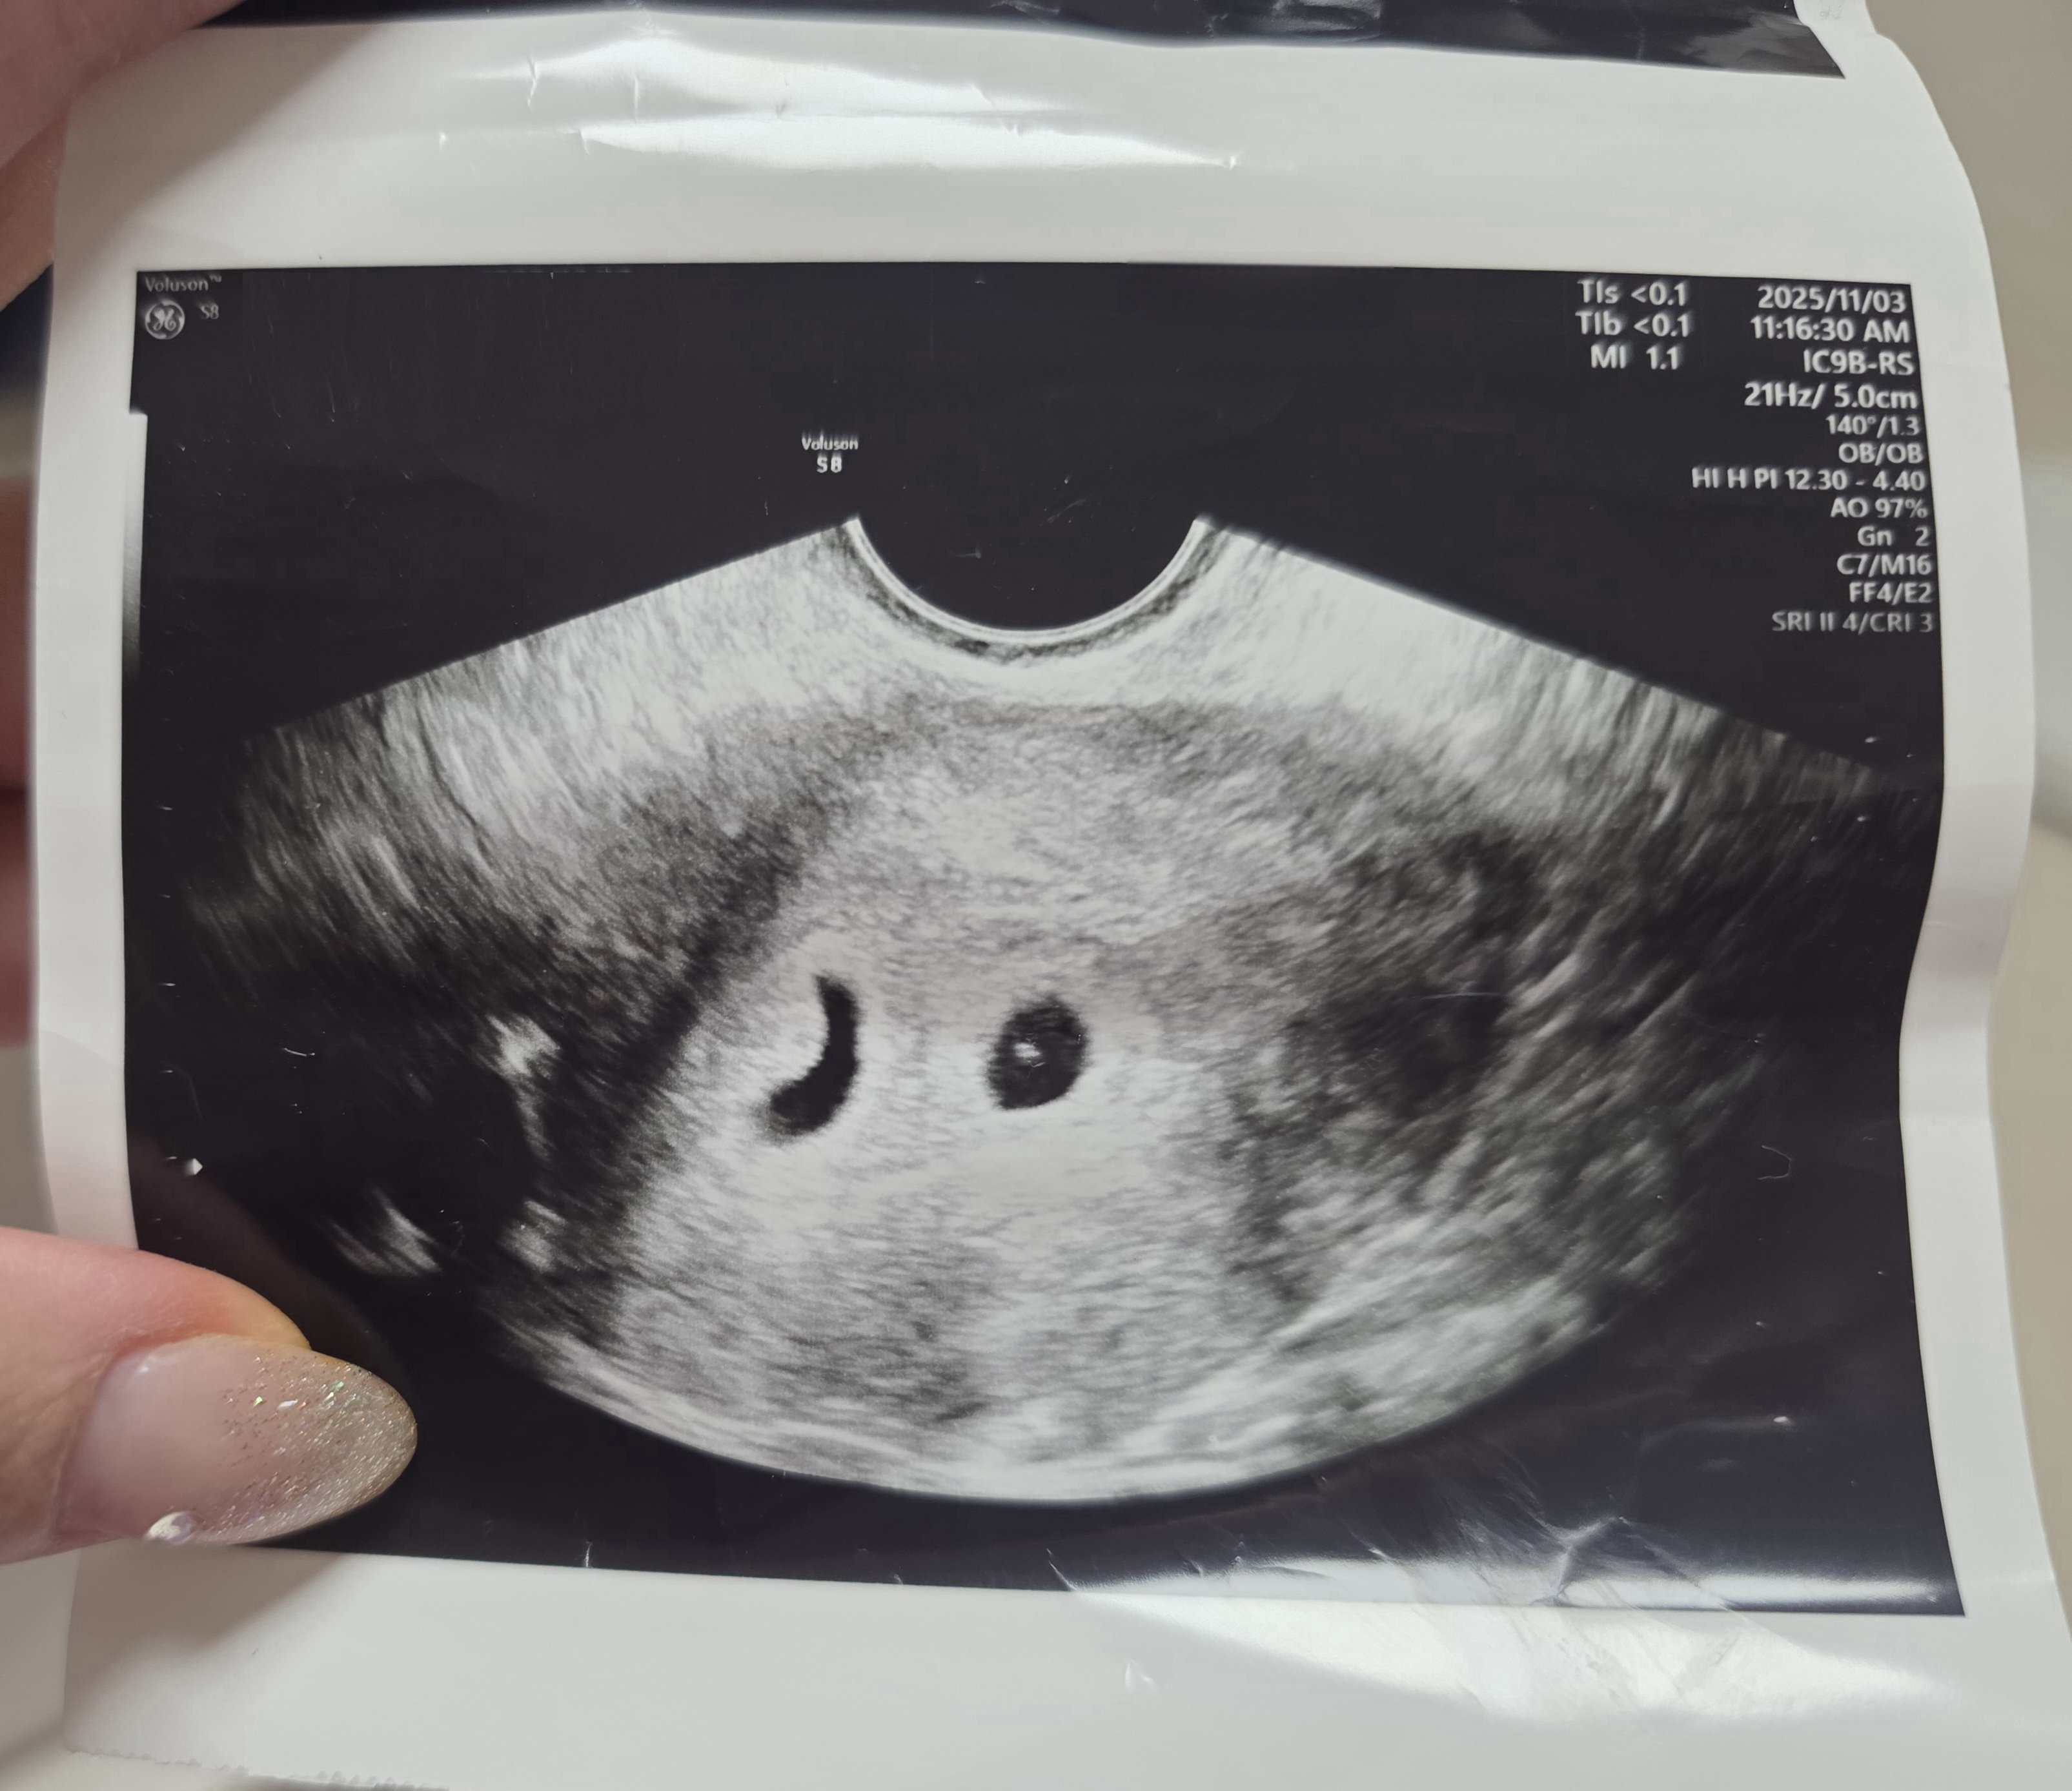

| 가슴 떨리는 임신 이야기를 공유해 주세요. | 결혼 후 8년 동안 임신 소식을 듣지 못하다가, 시험관 2차에 성공했을 때 가슴이 떨릴 만큼 벅찼습니다. 처음으로 아기집을 보고, 이어서 심장소리를 들었을 때의 감동은 아직도 선명하게 기억에 남아 있습니다. |

| 치료 도중 느꼈던 가장 기뻤던 순간과 절망적인 것들은 무엇인가요? 잊지 못할 경험이 있나요? | 가장 기뻤던 순간은 처음 아기집을 보고 심장소리를 들었을 때였습니다. 반대로 시험관 1차에서 착상에 실패했을 때는 너무 절망적이어서 마음이 많이 무너졌던 기억이 납니다. |